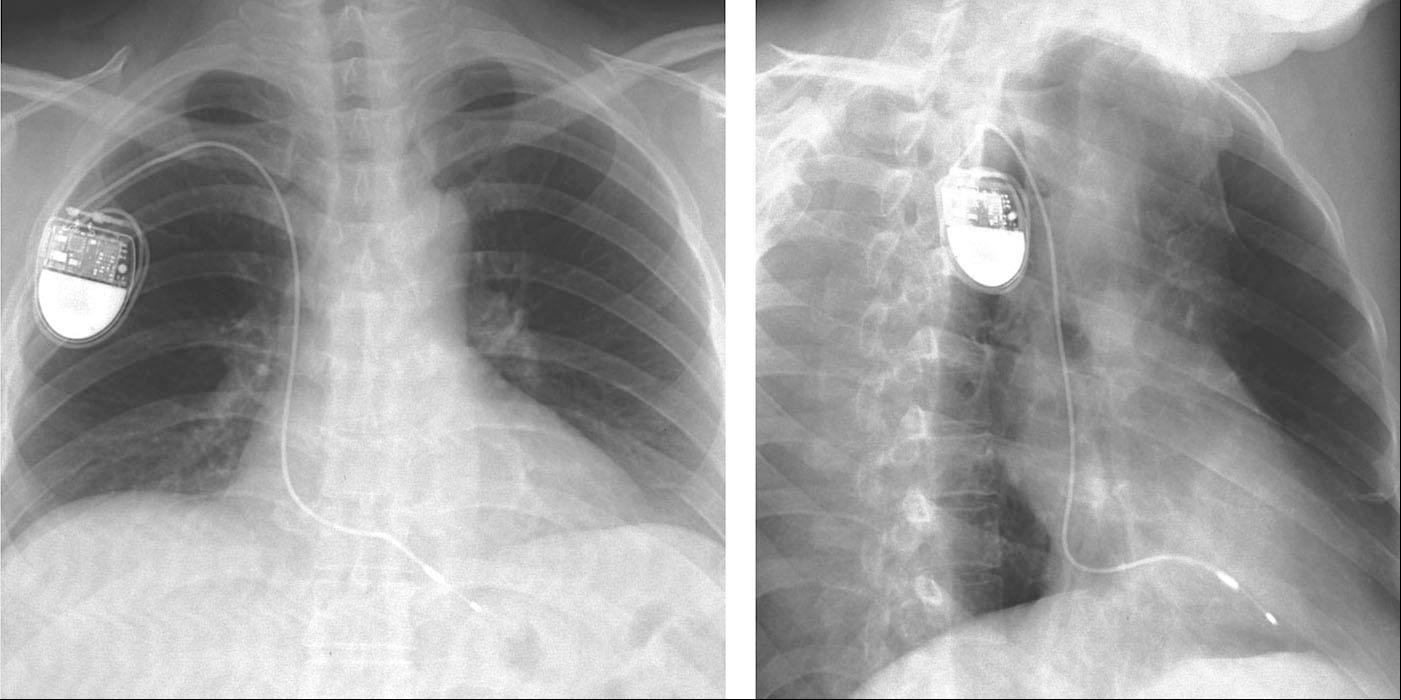

沿导引钢丝送入扩张管和套管,拔除套管后,沿扩张管送入起搏导线进入右心房。分别将心房、心室导线放置在合适位置。心室导线的可放置部位为右心室心尖部,也可放置在右心室其他选择性位点,如右心室流出道、右室间隔部及希氏-浦肯野系统(希浦系统),需要主动固定导线。主要步骤:①操作导线通过三尖瓣,证实导线在右心室。②放置导线在合适的右心室位点,导线头端稳定。③阈值测试符合要求。④导线保持合适的张力(图1-14)。心房导线常规固定在右心耳,也可以通过主动固定导线固定在右房其他部位如房间隔。嘱患者深呼吸、咳嗽。观察导线头端无移动,并保持合适的张力。

图1-14 合适的导线张力

心室导线放置在右心室心尖部,并保持合适张力。